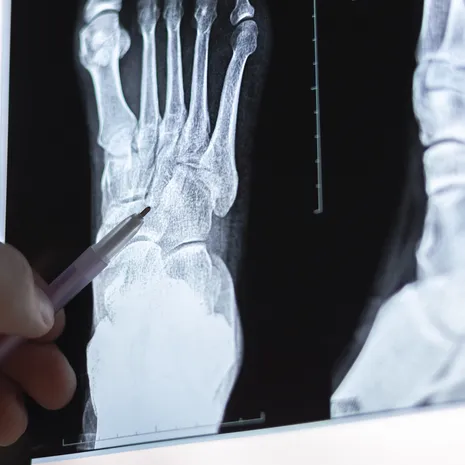

Stressfracturen

Veel lopen in schoenen zonder goede ondersteuning kan de botten en gewrichten extra belasten en leiden tot stressfracturen. Dit zijn kleine scheurtjes in de botten die vaak veel pijn veroorzaken.